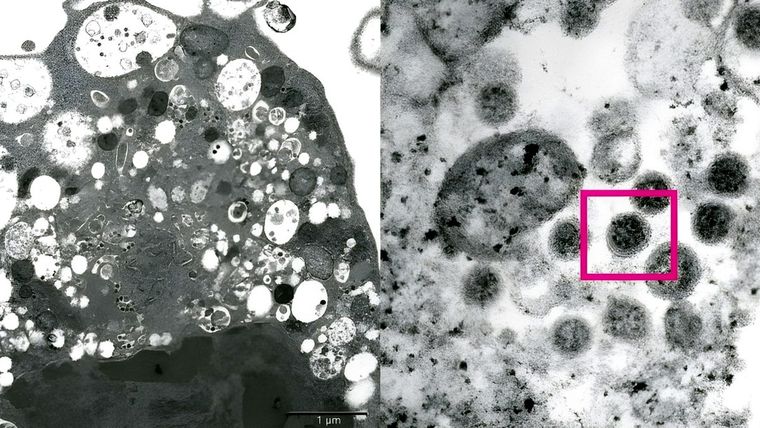

"La versión BA.2 presenta cinco mutaciones únicas en una parte clave de la proteína de espiga que el virus utiliza para adherirse a las células humanas e invadirlas, explicó a CNBC Troels Lillebaek, presidente del comité de Dinamarca que lleva a cabo la vigilancia de las variantes del covid-19. Las mutaciones en esta parte de la espiga, conocida como 'dominio de unión al receptor', suelen estar asociadas a una mayor transmisibilidad", aporta Rt.

Mientras, algunos expertos han apodado a BA.2 el 'ómicron sigiloso' porque tiene rasgos genéticos que hacen más difícil identificarlo en las pruebas de PCR. Asimismo, la OMS publicó que, a diferencia de la subvariante predominante, BA.2 "no causa una marca concreta en las pruebas de laboratorio denominada 'fallo de objetivo del gen S', lo que hace que pueda parecerse a otras versiones del coronavirus, como la delta, en un primer cribado". No obstante, esto no significa que no se la pueda detectar, sino que se hace de forma distinta.